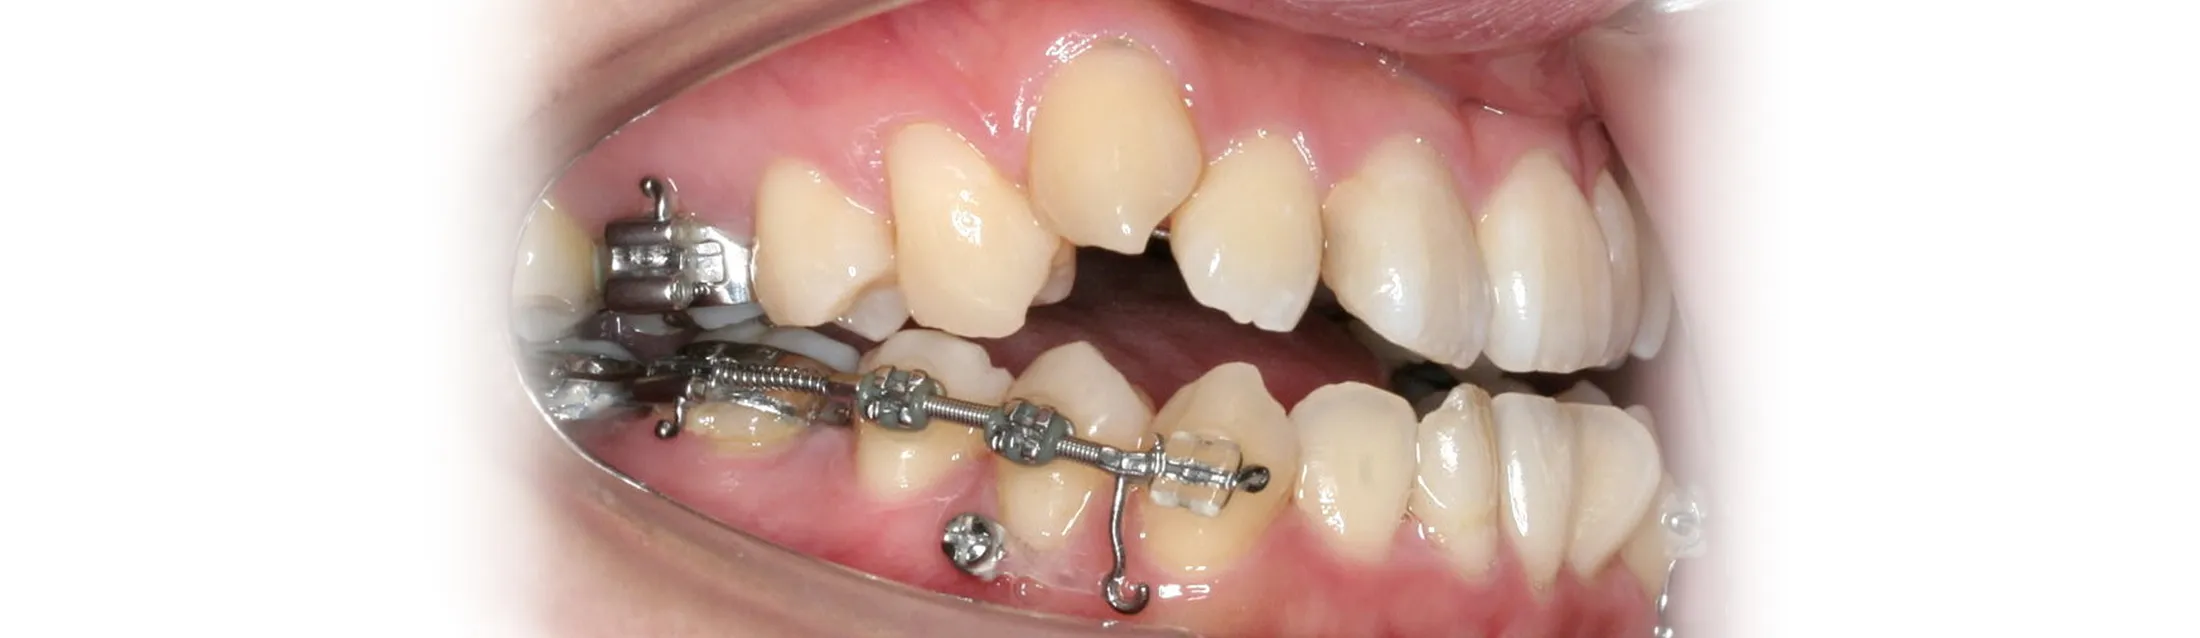

顎の骨に矯正治療用のアンカースクリュー(ねじ)を歯肉の下の骨に埋め込み、歯を動かすための固定源(支点)として利用する矯正治療法です。

通常のワイヤー矯正では、歯に装置を付けて互いに引っ張り合う構造のため、片側だけを動かしたい場合でも反対側の歯が一緒に動いてしまい、細かいコントロールが難しいという課題がありました。

アンカースクリューは埋め込んだ骨にしっかり固定されるため固定源が動かず、狙った方向に正確に歯を移動させることが可能です。従来では難しかった歯の移動や治療期間の短縮にもつながり、対応できる症例の幅が大きく広がりました。

歯科矯正用アンカースクリュー